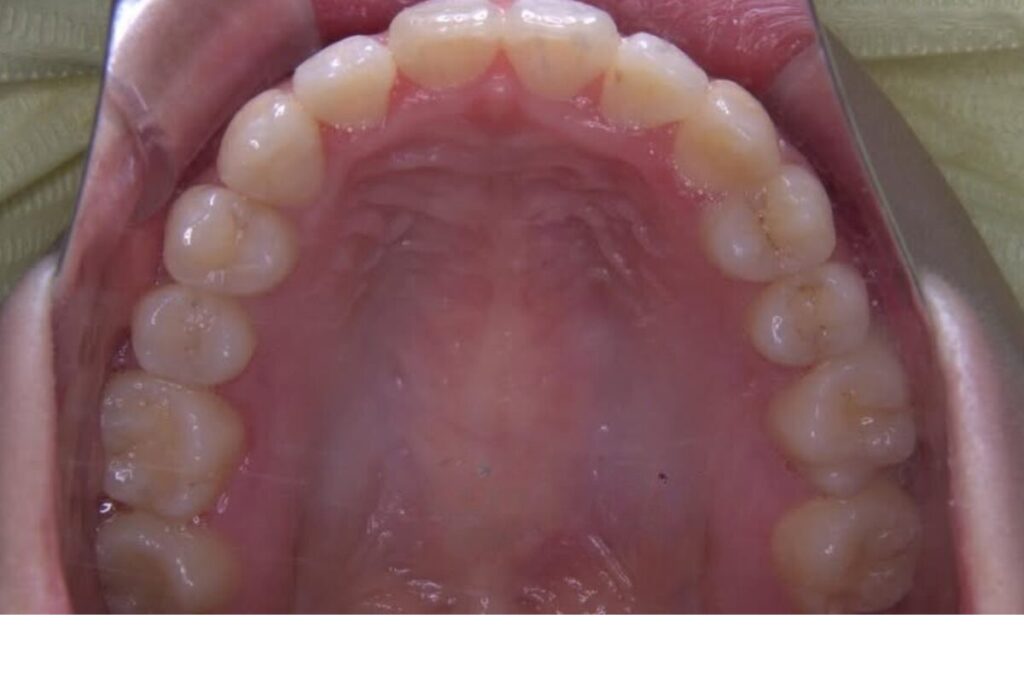

| 患者 | 28歳男性 |

|---|---|

| 主訴 | 歯ならびのガタガタ |

| 診断名 | UR7/LR7クロスバイトと上下叢生を伴うAngleⅠ級sk.1不正咬合 |

| 治療内容 | マウスピース型矯正装置(インビザライン)、部分的に上顎前歯部にワイヤー併用 |

| 抜歯の有無 | 非抜歯 |

| 治療期間 | 2年 |

| 費用(税込) | 594,000円 |

| リスクと副作用 | 痛み等、歯根吸収/歯肉退縮、後戻り、むし歯・歯肉炎の可能性。 |

【医師コメント】

上下のガタつきで来院された患者さんです。

精密検査の結果、UR7/LR7のクロスバイト(交叉咬合)と上下の叢生を伴う AngleⅠ級(sk.1)不正咬合 と診断しました。奥歯の前後関係はⅠ級で大きなズレは強くない一方、奥歯の噛み合わせのズレとスペース不足が原因でした。

治療はインビザラインを主体に非抜歯で計画し、歯列全体のバランスとかみ合わせの安定を意識しながら段階的に改善を進めました。

終盤、UL2のローテーションがわずかに残ったため、仕上げの精度を高める目的で上顎前歯部に部分的にワイヤーを併用しています。

治療は計画に沿って進行し、2年で歯列の配列とかみ合わせの改善を図ることができました。